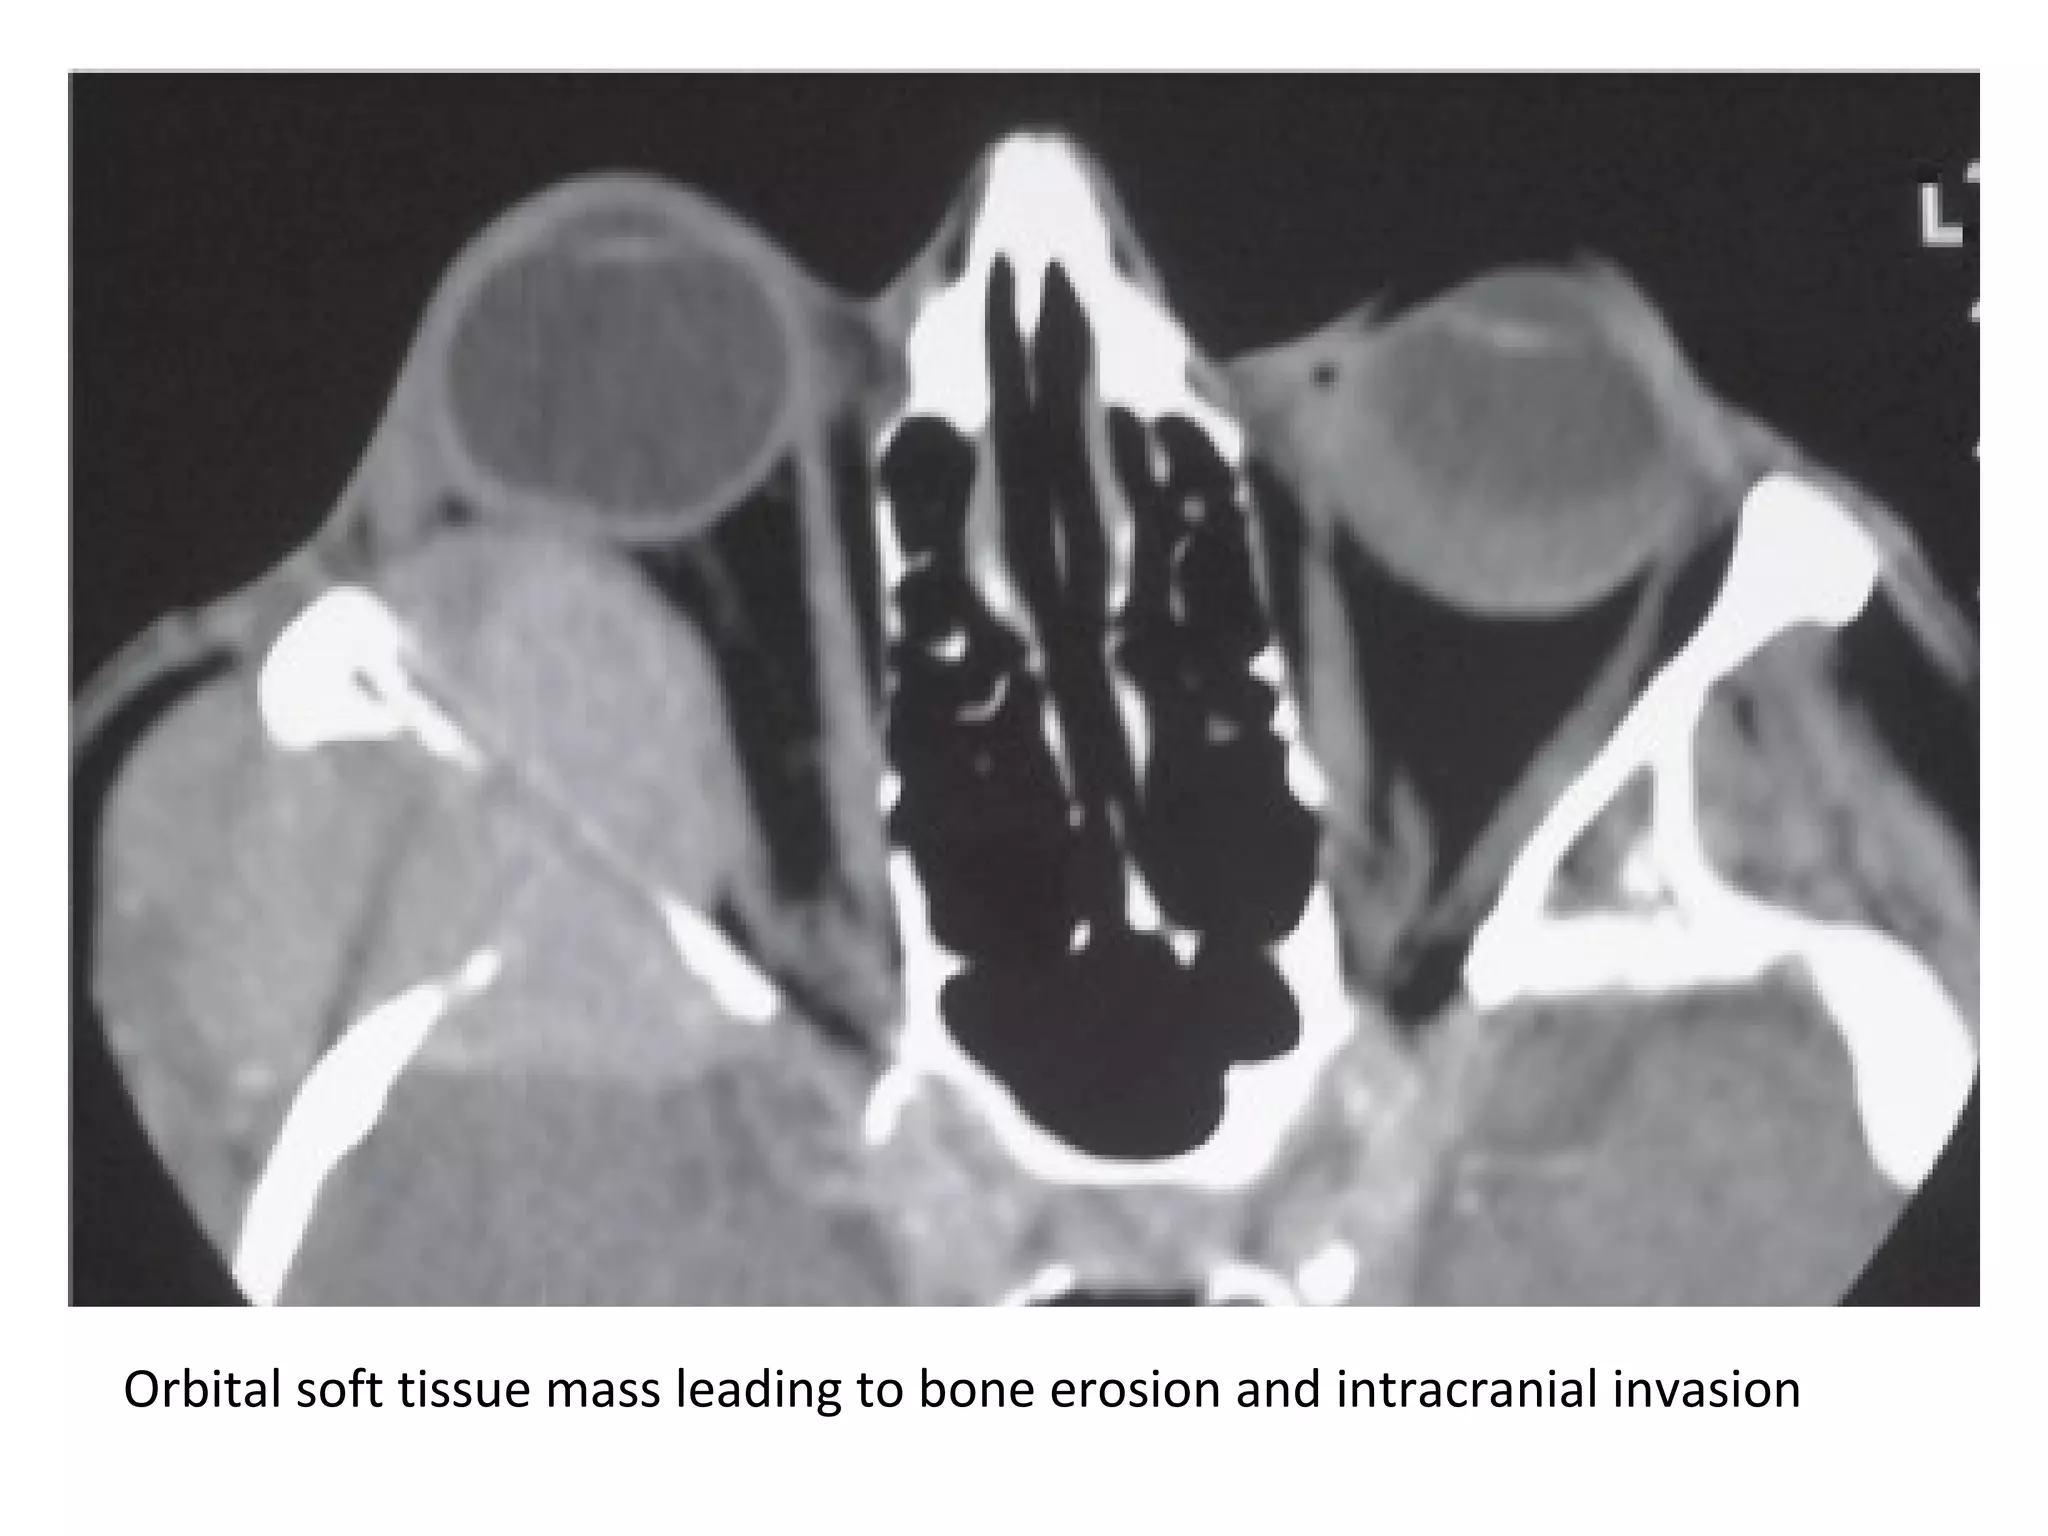

Orbital soft tissue mass leading to bone erosion and intracranial invasion

Breast cancer metastasis in a 56-year-old woman who presented with eye

pain, axial T1+C fat-suppressed shows thickening of the left lateral rectus

muscle (arrows), with involvement of the tendinous insertion, biopsy

results revealed breast cancer, which was undiagnosed at presentation